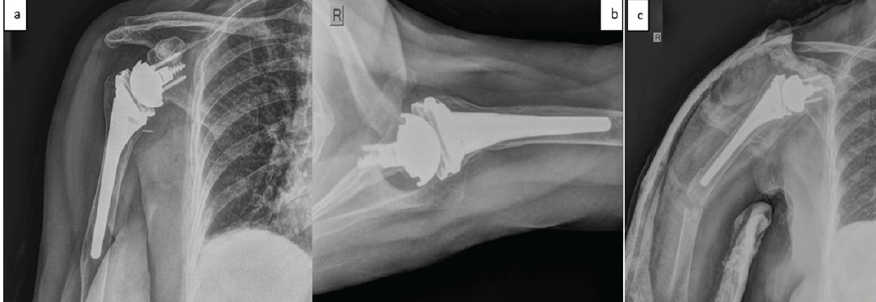

An 80-year-old female patient with a known history of systemic hypertension and severe osteoporosis presented to the emergency room (ER) with a history of a fall and was diagnosed to have a periprosthetic fracture of the right humerus (Figure 1) and an extrarticular fracture of the left distal radius.

Figure 1: Anteroposterior and lateral radiographs showing well-functioning reverse total shoulder arthroplasty [R] and well-fixed uncemented prosthesis with severe osteopenia (a and b). Anteroposterior radiograph showing periprosthetic fracture, Wright and Cofield classification Type B with stable prosthesis (c).